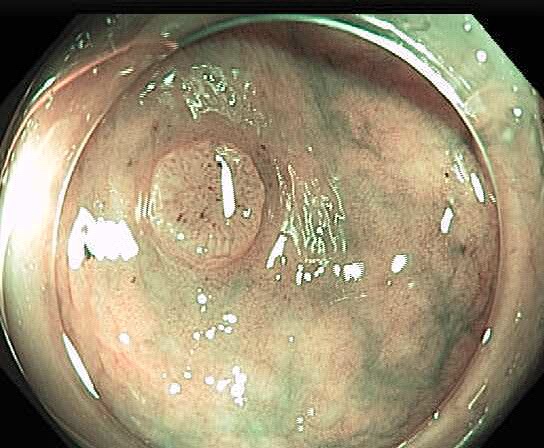

Colonoscopy is the main diagnostic procedure to detect and recognize polyps located on colorectal walls. The accurate detection and correct classification depend on the skills and experience of the endoscopists, however, even for experienced endoscopists, working on conventional colonoscopy for long hours leads to mental and physical fatigue and degraded analysis and diagnosis. Other factors that may affect the classification results include varying illumination conditions, variant texture and appearance, and occlusion. Moreover, different types of polyps are hard to differentiate since they may exhibit a very similar appearance with a subtle difference, as shown in Fig 1. It requires a thorough examination of fine details to distinguish one category form the other. Therefore, an accurate and effective automatic computer-aided system for colonoscopy is required to help endoscopists to detect and classify the type of polyps. This automated recognition mechanism can also be used as a second opinion to determine whether a further biopsy is required for diagnosis, which in turn will greatly reduce the cost of diagnosis. In addition, such an intelligent system can also be used as an educational resource for gastroenterology trainees to reduce the learning curve and cost.

![]() |